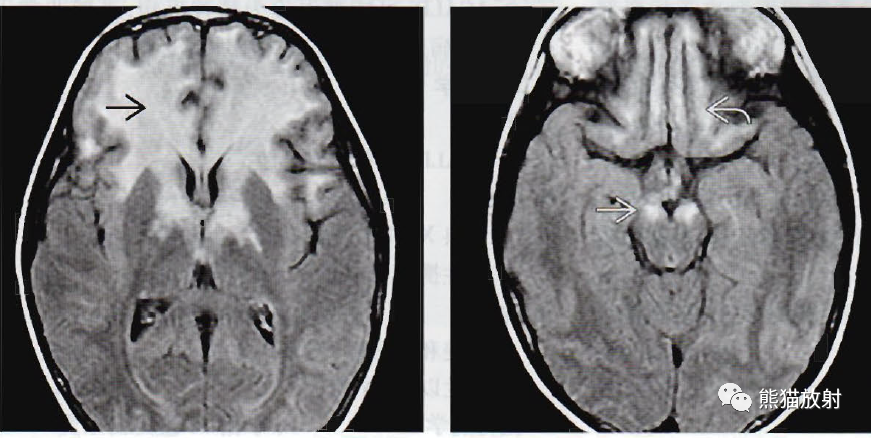

(左) 轴位FLAIR显示融合性双侧白质高信号。这位已经证实为X-ALD的学龄期男性病例(Loes 2型) ,为大脑前部受累的变异型,异常信号延伸入尾状核头、苍白球和内囊前肢。

(右)同一位患者,轴位FLAIR显示内囊的对称白质高信号延伸入大脑脚(直箭)和额叶皮质下白质(弯箭)。